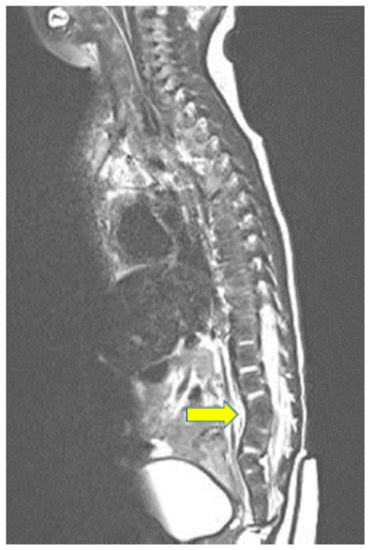

2. Case Report